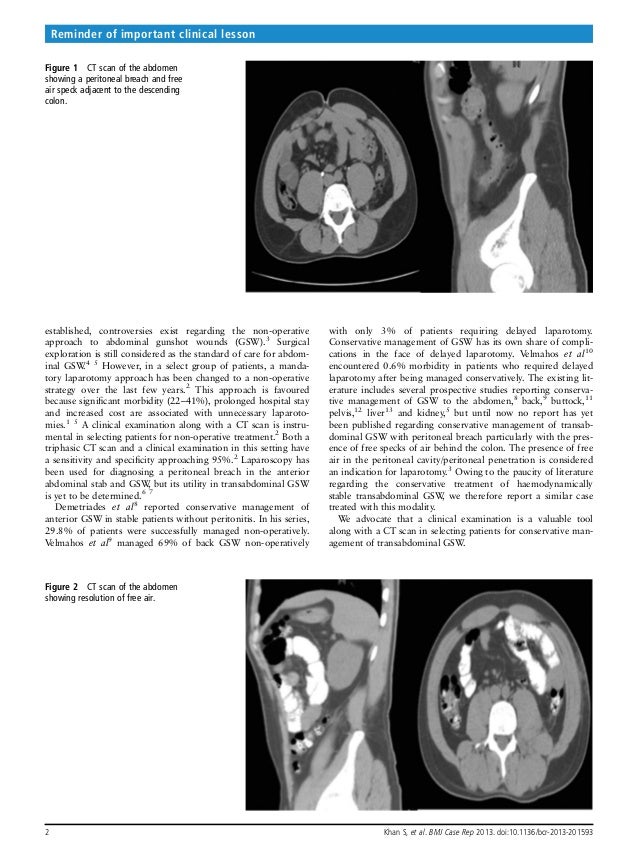

BMJ Case Reports2013Khanbcr2013201593

BMJ Case Reports2013Khanbcr2013201593 Bmj Case Report Abstract A case report is a way of communicating information to the medical world about a rare or unreported feature, condition,. Each article type has a unique writing template. The largest online collection of medical. There is no need to go into detail in terms of the background to the study, as those who are reviewing the abstract will have some.. Bmj Case Report Abstract.

BMJ Case Reports2013Khanbcr2013201593 Bmj Case Report Abstract There is no need to go into detail in terms of the background to the study, as those who are reviewing the abstract will have some. The largest online collection of medical. Bmj case reports publishes clinical case reports, global health case reports and images. Case reports written without guidance from reporting standards are insufficiently rigorous to guide clinical practice. Bmj Case Report Abstract.